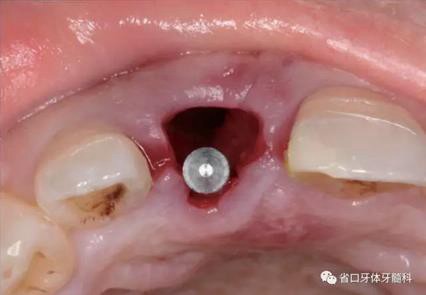

(2)制備臨時(shí)冠:術(shù)后當(dāng)天取模轉(zhuǎn)移,送工廠以Zimmer®多功能 攜帶體為臨時(shí)基臺(tái)制備臨時(shí)修復(fù),獲得舌隆突開孔螺絲固位的烤塑臨時(shí) 冠。將其就位于口內(nèi)種植體,調(diào)整正中、前伸及側(cè)方咬合無接觸,加力 10~15N·cm,可見即刻修復(fù)體良好地支持齦緣及牙齦乳頭結(jié)構(gòu)。

圖22 臨時(shí)冠就位前袖口檢查

圖23 就位臨時(shí)冠

圖24 臨時(shí)冠咬合調(diào)整